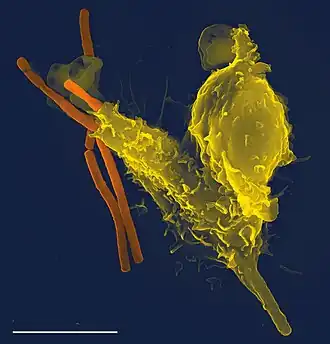

A rapidly moving neutrophil can be seen taking up several conidia over an imaging time of 2 hours with one frame every 30 seconds.

A neutrophil can be seen here selectively taking up several Candida yeasts (fluorescently labeled in green) despite several contacts with Aspergillus fumigatus conidia (unlabeled, white/clear) in a 3-D collagen matrix. Imaging time was 2 hours with one frame every 30 seconds.